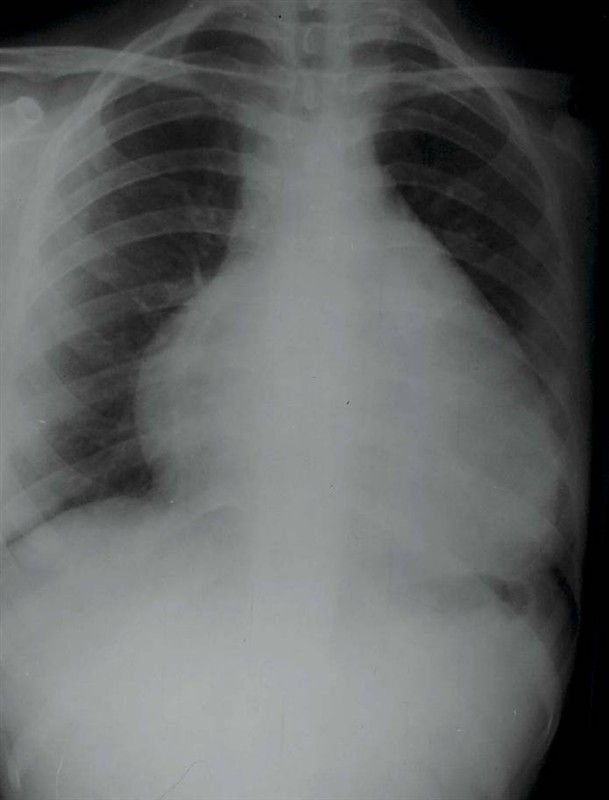

照片名称:大量胸腔积液